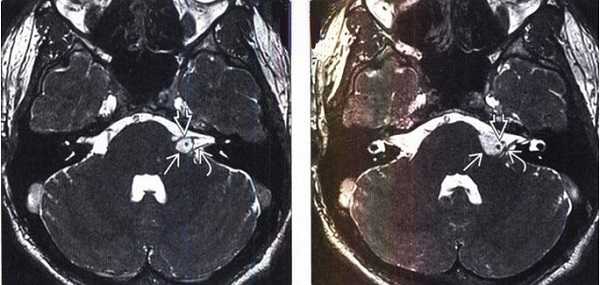

Липома ММУ (указана стрелками) на снимке МРТ головного мозга в аксиальной проекции

МРТ головного мозга. На мрт в аксиальной плоскости отмечается объемное образование внутреннего слухового прохода слева (стрелка), с четкими и неровными контурами, деформирующее окружающие структуры. После внутривенного введения парамагнитного контрастного вещества отмечается интенсивное и неоднородное его накопление образованием (изображение справа) — невринома.